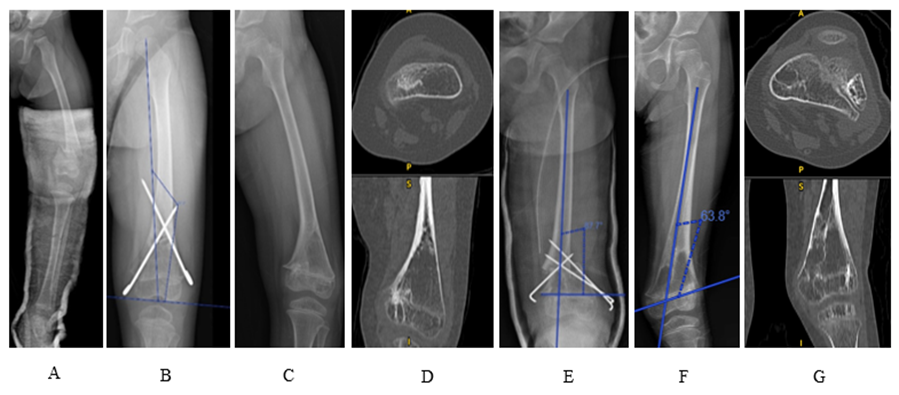

This high-impact polytrauma case involved a two-year-old girl who sustained closed left supracondylar femoral fractures, (Figure IA), a brain injury and a right pneumothorax after motor vehicle accident. Closed reduction and transphyseal cross K-wiring of the distal femur were performed (Figure IB). The K-wires were removed 10 months later.

She represented two and a half years later with a progressive varus deformity of the left distal femur (Figure IC). A computed tomography (CT) scan confirmed the formation of a medial physeal bar (Figure ID). At age of five, she underwent medial physeal bar resection with bone wax interposition and valgus osteotomy (Figure IE). The K-wires were removed two months postoperatively.

One year later, the distal physis of the left femur developed a lateral physeal bar, resulting in valgus deformity (Figure IF). A CT scan revealed the formation of a new lateral physeal bar (Figure IG). Therefore, at age of six, a second surgery involving lateral physeal bar resection and varus corrective osteotomy were performed to correct the valgus deformity (Figure II A & IIB).

Figure I: A: displaced supracondylar fracture of left femur at age of two. B: left femur was treated with cross K-wires that passed through distal femoral growth plates. C: varus deformity of distal femur with medial physeal bar formation in Sept 2020. D: CT image in Jan 2020 which medial physeal bar identified. E: physeal bar resection followed by corrective osteotomy and fixation with 1.6mm wire performed at the age of 6 (Sept 2020). F: The distal femur became valgus in Dec 2021 (6 years old) to suggest a successful medial physeal bar resection and physeal bar formation on lateral side. G: CT image in Dec 2021 showed a very lateral location of physeal bar.